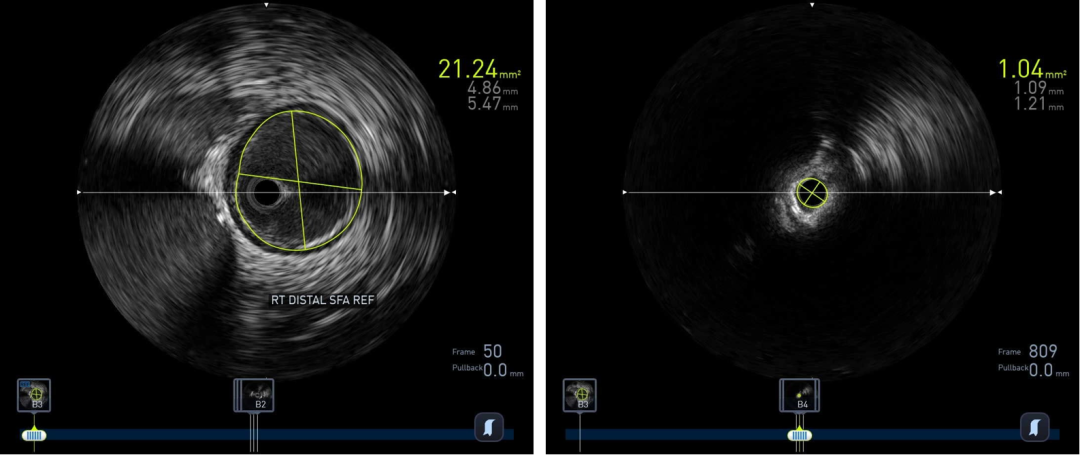

图:IVUS测量

图:Diamondback 360 减容

精准评估先行:综合运用超声、CTA、DSA,特别是IVUS,明确斑块性质(软/硬/钙化)、分布(偏心/环形)、位置(内膜/中膜)以及血栓负荷。这是所有决策的基础。

原则上真腔通过病变,最好IVUS证实。